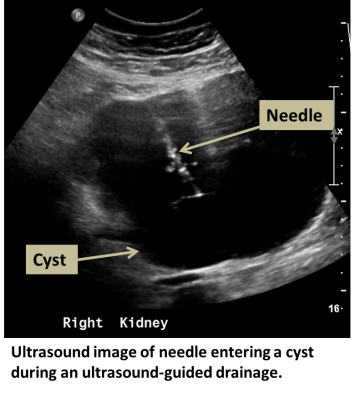

An interventional radiologist or abdominal radiologist uses CT or ultrasound to guide a needle or small drain into one or more cysts. The fluid is then removed by vacuum suction. If cysts are recurrent, sclerosis can be performed by instilling a chemical which damages the cyst wall, reducing its chance of recurrence.